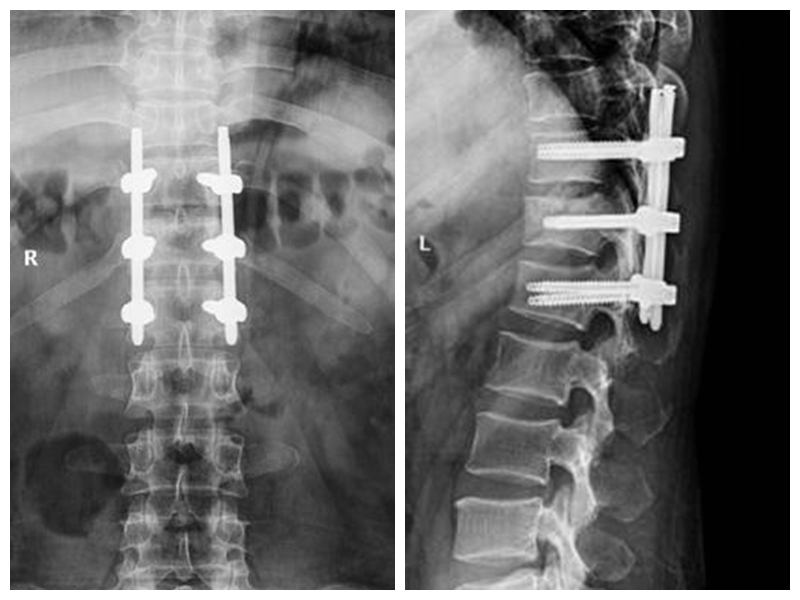

经皮胸腰椎骨折椎弓根螺钉内固定技术

传统胸腰椎骨折切开复位椎弓根螺钉内固定术组织创伤大、失血量大、住院时间长、下地时间晚、费用高。经皮胸腰椎骨折椎弓根螺钉内固定技术组织创伤小、失血少、住院时间段、下地时间早、费用低。

典型病例:患者**,男性,43岁,因“摔伤致胸腰背部疼痛、活动受限2小时”门诊平车入院。双下肢肌力、感觉及肌张力正常。

本例患者术后5天在腰围保护下独立下床,双下肢肌力感觉正常。